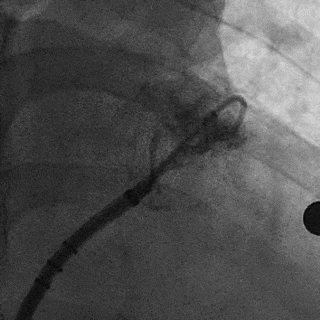

术中DSA左心耳造影+测量确认心耳形态和位置

右肩位左心耳造影

肝位左心耳造影

DSA左心耳造影

(正足位造影)